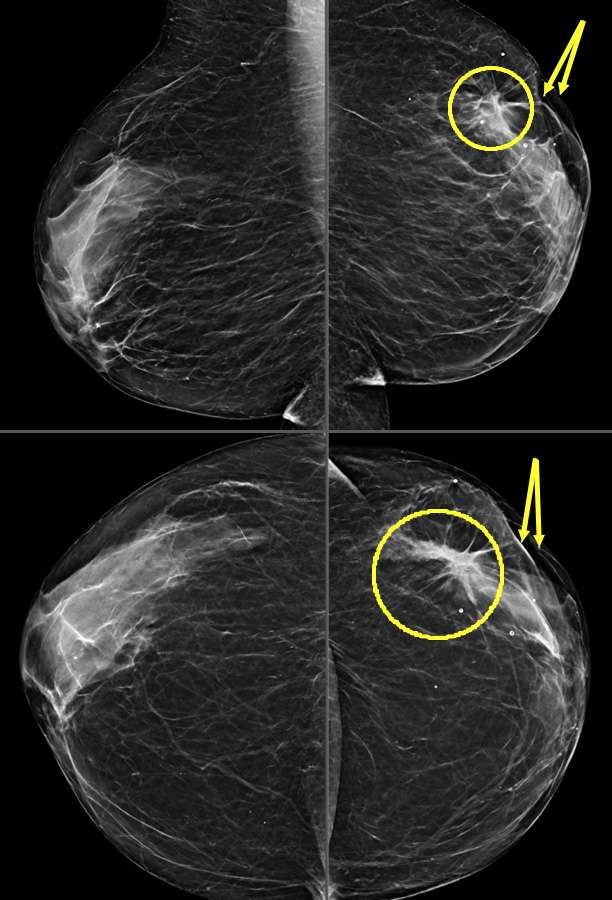

Figure 3: Nipple Retraction on mammogram. Patient presented for right nipple changes. Mammographic MLO and CC projections demonstrate a retracted nipple (arrows) overlying an irregular mass in the subareolar region with associated architectural distortion (circles) in the right breast. Left breast included for comparison.